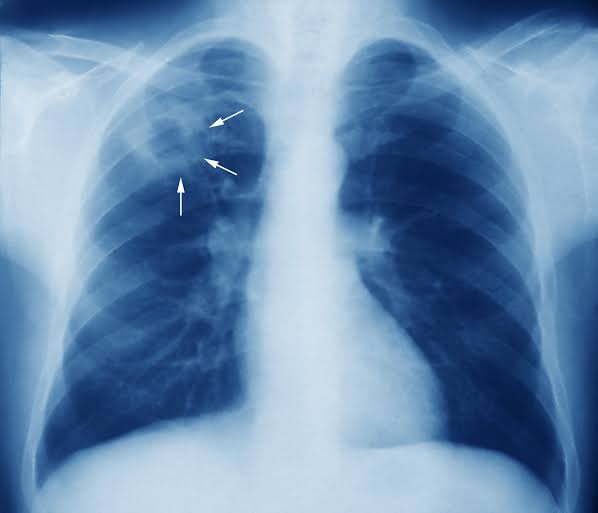

TB is a potentially serious infectious bacterial disease that mainly affects the lungs. It is caused by a germ. This is different from a virus like the one which causes Covid-19. You understand?

When symptoms do occur, they usually include a cough (sometimes tinged with blood), weight loss, night sweats and fever. Treatment isn’t always required for those without symptoms. This is because most often we don’t know who they are.